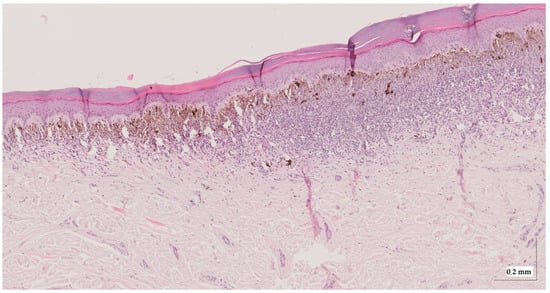

Appendix A. Selected Cases Studies’ HE Histopathological Images (Limited to OCT FOV)

| Superficial spreading melanoma (SSM) Case 2 | Localization: right forefoot (right ankle) |

![]() | ![]() |